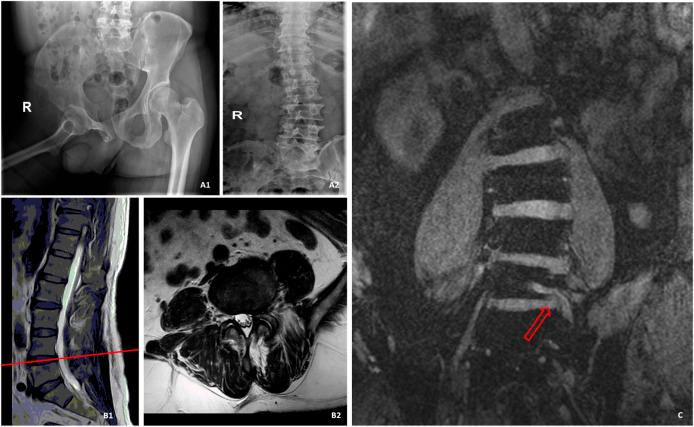

The aim of this study was to explore the significance of three-dimensional double-echo steady-state (3D-DESS) sequence and multidetector computed tomography (CT) plain scan in the diagnosis of lumbar disc herniation (LDH) remaining controversial in conventional magnetic resonance imaging (MRI), and to compare the efficiency between 3D-DESS and CT in diagnosing controversial patients by conventional MRI. A total of 61 patients with controversial LDH diagnosed by conventional MRI were collected. Before operation, the disease of these patients was further confirmed by 3D-DESS sequences and continuous CT plain scan from L3 to S1. Finally, for patients whose postoperative curative effect was marked and symptoms were obviously alleviated, the sensitivity, specificity and accuracy. Among, 59 patients with remarkably relieved symptoms after operation were included, and 2 patients with varying degrees of non-remission of pain and partial dysfunction after operation were excluded. The sensitivity, specificity and accuracy of 3D-DESS were 94.6, 100 and 94.9%, respectively, and those of CT were 75.0, 33.3 and 72.9%, respectively. 3D-DESS is a very useful diagnostic method for patients with some special types of LDH that remain controversial in conventional imaging diagnostic methods. Through 3D-DESS, the morphology of lumbosacral nerve roots can be directly observed, which is conducive to the improvement of the sensitivity, specificity and accuracy, thus further reducing the misdiagnosis rate. Moreover, 3D-DESS plays a guiding role in the formulation of operative methods.

本研究旨在探讨三维双回波稳态(3D-DESS)序列和多排螺旋计算机断层扫描(CT)平扫在常规磁共振成像(MRI)中仍存在争议的腰椎间盘突出症(LDH)诊断中的意义,并比较3D-DESS和CT在通过常规MRI诊断存在争议患者方面的效率。共收集了61例经常规MRI诊断为存在争议的LDH患者。术前,通过3D-DESS序列以及从L3至S1的连续CT平扫对这些患者的病情进行进一步确认。最后,对于术后疗效显著且症状明显缓解的患者,评估其敏感性、特异性和准确性。其中,纳入了59例术后症状明显缓解的患者,排除了2例术后疼痛不同程度未缓解且存在部分功能障碍的患者。3D-DESS的敏感性、特异性和准确性分别为94.6%、100%和94.9%,CT的敏感性、特异性和准确性分别为75.0%、33.3%和72.9%。对于一些在传统影像诊断方法中仍存在争议的特殊类型LDH患者,3D-DESS是一种非常有用的诊断方法。通过3D-DESS,可以直接观察腰骶神经根的形态,有利于提高敏感性、特异性和准确性,从而进一步降低误诊率。此外,3D-DESS在手术方法的制定中发挥着指导作用。